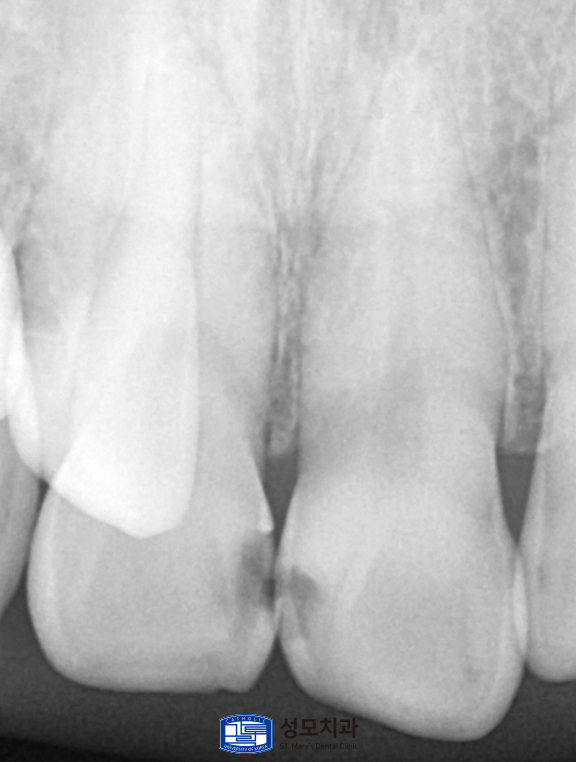

파란색으로 표시된 상악 전치부 첫 번째 앞니의

사이 인접면에는 초기 우식과 변색이 동반되어 있었습니다.

심미와 발음이 민감한 상악 첫 번째 전치의

사이 인접면은 레진으로 수복했습니다.

가능한 충치 부위만을 보존적으로 제거하고

주변 치아와 조화되는 색과 투명도를

레진 재료를 통해 재현했습니다.

마무리 연마를 충분히 시행해

변연을 매끈하게 다듬어

치실 사용 시 걸림이 없도록 했습니다.